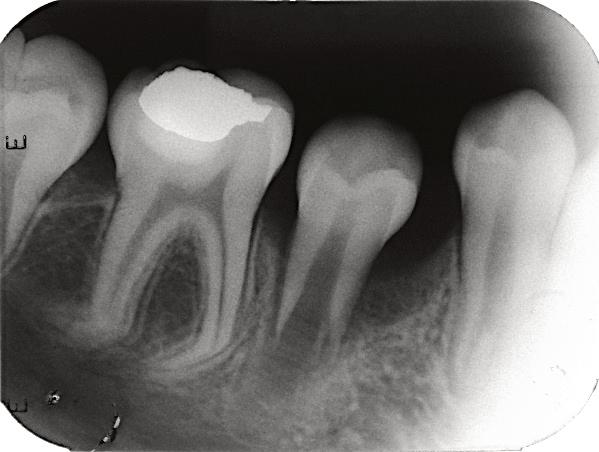

8.Biodentine®AnalternativeinVitalPulpTherapyinYoungPermanentTeeth.ClinicalCase,40monthFollow-Up. (Pgs.88-96)

Biodentine®UnaalternativaenlaTerapiaPulparVitalenDientesPermanentesJóvenes.CasoClínico.Seguimientode40Meses.

LuisDavidRamosFlores,DDS,